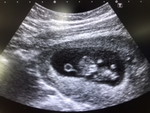

กำลังจะมีลูก